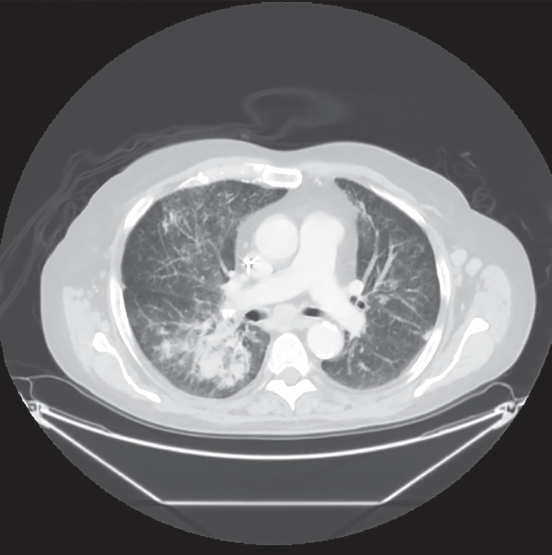

Rayhan Lal, MD; Cynthia H. Ho, MD; Daniel Edberg, MD

A 16-year-old boy presented to the emergency department with 2 weeks of worsening lower abdominal pain.